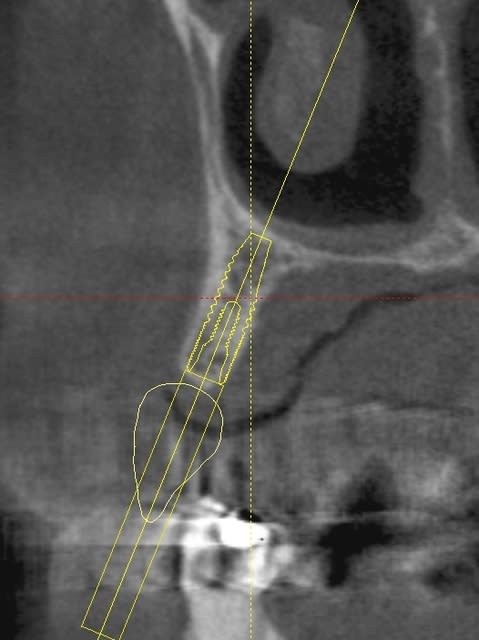

une petite étude de ton cas avec implants osseosped Astra :

12 : 3.5 x 11

13 : 3 x 11 (?)

14 : 3 x 11 (?)

15 : 3.5 x 11 (?)

16 : 4 x 11

17 : 4 x 11

je ne pratique pas donc pas de conseils sur ces implants.

techniquement:

extraction de 12 , curetage soigneux.

vue la qualité osseuse :

si D4 :

saignée à la lame n°15

si D3 :

avec un disque diamanté 10 x 0.3mm incision crestale de 12 à 16 ou 17

puis avec un disque de 20x0.3mm ou à la lame 15 approfondissement de la saignée

puis expansion en "douceur" (sans incision de décharge verticale, à priori car la ligne de crête est relativement droite)

pose de tes implants et dans ce cas, le VitalOs me semble idéal.

la difficulté majeure sera la corticale palatine qui ne semble pas géniale et qui méritera une attention particulière, ostéotome de Tatum +++

honnêtement je ne commencerais pas par un cas comme celui ci sans une solide connaissance de la sensibilité osseuse.

pas de provisoire